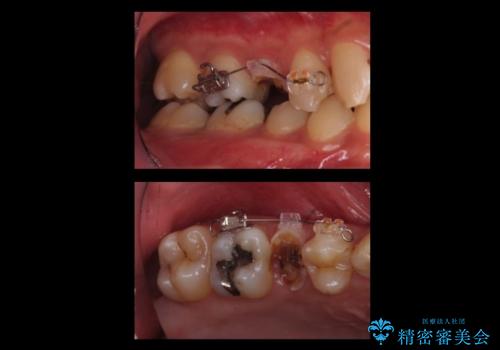

放置した虫歯 歯ぐきの中まで虫歯でも、しっかり健康的な部分を引っ張り出して、きちんと処置します。

- 放置した虫歯の治療で来院。

歯茎の中まで虫歯になっており、そのまま完璧に治療をすることは不可能でした。

歯の健康な部分を矯正治療で引っ張り出してから、虫歯治療を行なっています。

開始前

治療途中